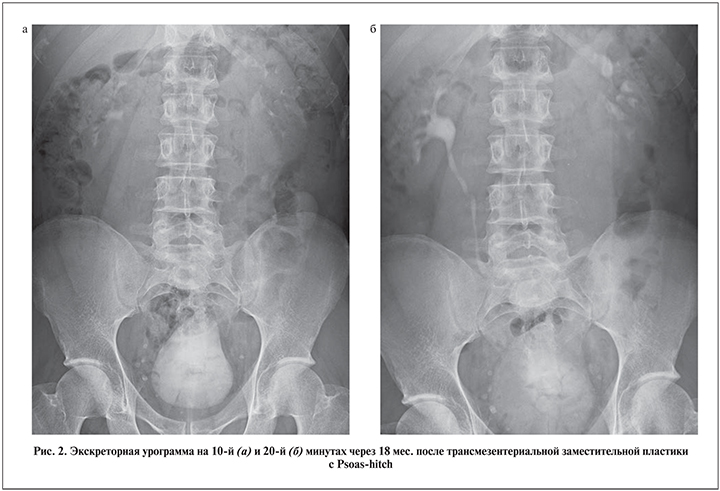

Лишь 4 из 40 наших больных проигнорировали программу послеоперационного мониторинга в связи с низким комплаенсом. Изучив катамнез 36 пациентов в сроки от 6 мес. до 7 лет, мы не обнаружили каких-либо отсроченных осложнений, значимых метаболических или уродинамических нарушений, равно как и угнетения функции почек (рис. 2, 3).